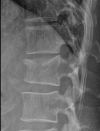

• zuzla

foto z CT

Husté :-(

To ho jako chtějí v tomto stavu jen tak pustit domů, aby začal běhat? Vždyť ten obratel se teď bude pomaličku narovnávat a nikdo neví, co to udělá s ním a kam se posunou ty úlomky. Už jen z tohoto důvodu, aspoň co vím, by měl pár týdnů jen ležet i když půjde vše dobře.

Z rentgenu neškolené oko většinou nic nepozná, ale tady je na první pohled vidět, že hrubě něco není v pořádku. Snaž se ho dostat na neurochirurgii, ať o tom rozhodne neurochirurg a ne někdo, kdo dává dlahy na zlomená předloktí.